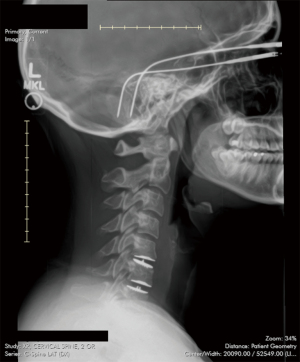

The patient was identified on physical examination to have diminished sensation in the right fourth and fifth finger (C8) and the left shoulder, radial aspect of forearm, thumb, index finger, and middle finger (C5 and C6). The reflex examination was 2+ throughout except for the left biceps and triceps which were 3+. The patient had 5/5 strength in all muscle groups in the upper and lower extremities. There was tenderness of the paraspinal musculature posteriorly. The patient had limited range of motion on account of pain in the neck. Patient was determined to have cervical disc disease with disk disease associated with C5–C6 and C6–C7 (Figures 1,2).

Figure 1 T2 sagittal magnetic resonance imaging demonstrating herniated disc of C5–C6 and C6–C7.